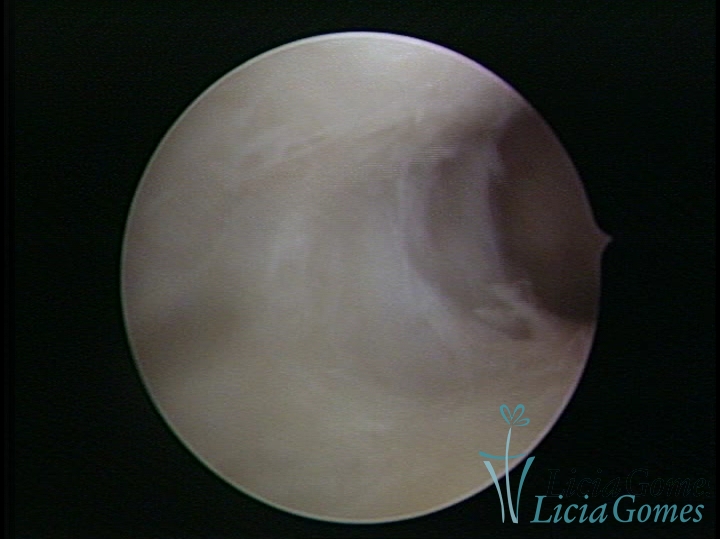

FIBROUS SYNECHIA

Uterine synechiae are scars (adherence) between the surface of the uterine walls, which may occur after the surgical procedure, uterine curettage, or after an inflammatory process in the uterine cavity (endometritis), which may lead to menstrual changes, infertility and obstetric complication such as abortion and premature birth.

SINÉQUIA TIPO MUCOSA